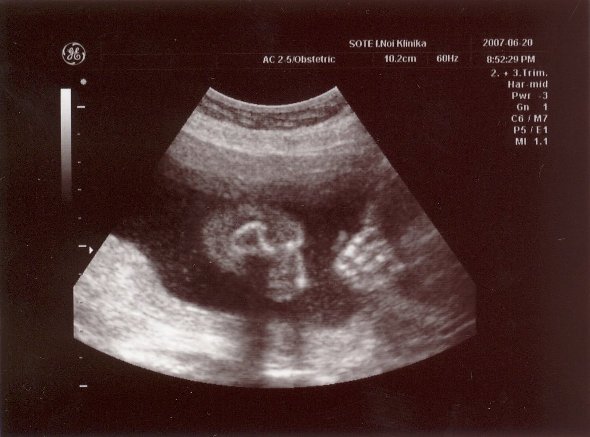

Voltam ma NST-n. Minden okés volt, bár a bébi nem nagyon akart mocorogni... Szerintetek is normális ugye, hogy mostmár kevesebbet mocorog? Főleg, ha megtalálta a helyét fejjel lefelé...?!

Gyönyörű a kislányod a képen, annyira csodálatos, hogy ennyire látszik mindene! HIdd el, nemsokára mindannyian a kezünkbe tarthatjuk őket, és mi leszünk a legboldogabbak a világon!!!

Nagyon szép az uh-os képed!

De irigykedek rá, hogy láttad a haját! Én is hajasbabát szeretnék!!!

RAkok nektek egy mai pocak képet